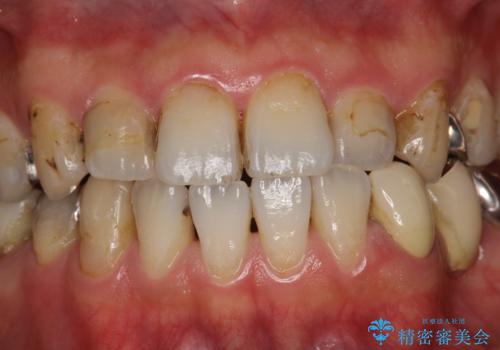

治療のスタート前に着色・ステインをPMTCできれいに除去

歯の表面に、茶色く色が残っている所がありますが、これは詰め物の変色の所と、虫歯になっている所です。以前に、CR(コンポジットレジン)による虫歯治療がされています。

CRは経年的劣化や、着色してしまうことがあります。PMTCでクリーニングを行うと、古いCRが目立つことがあるため、気になる際は詰め替えを行います。

茶色くなっている部分が、着色なのか、劣化なのか、虫歯によるものなのかは判別が難しいことがあります。そのため、定期的にPMTCを行うことで状態の確認が的確に行えます。

また、治療が開始される前などにも、全体的にクリーニングを行いご自身本来の歯の色、状態を精密に確認することが大切です。